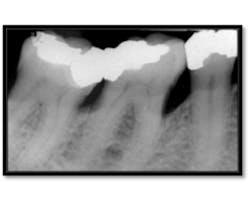

As you can see, calculus is visible on the mesial surfaces of both molars and the extent of bone loss mesial of # 30 is significant. 18 months post treatment:

Pocket depths are now 2-5mm (above left), Notice the nice bone fill on the mesial of both molars (above right)

A one-year follow up of a retrospective analysis of patients receiving Micro Ultrasonic Endoscopic Periodontal Debridement shows a dramatic reduction in probing depths in all types of teeth, particularly in deeply pocketed posterior teeth, as the above case demonstrates. Some perioscopy users incorporate adjunctives and or other therapy into their non-surgical protocol, such as Arestin, Emdogain (an enamel matrix derivative), and lasers.